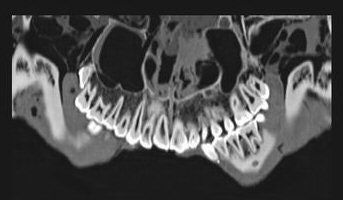

![]() |

| Dental image taken of the mummy of King Tut. Image courtesy of Egypt's Supreme Council of Antiquities. |

King Tut's bones indicate that he had a slight build, was well-fed and healthy, and had not suffered from major childhood malnutrition or infectious diseases, the team reported. The king also had a slightly cleft palette and an impacted wisdom tooth, they added.